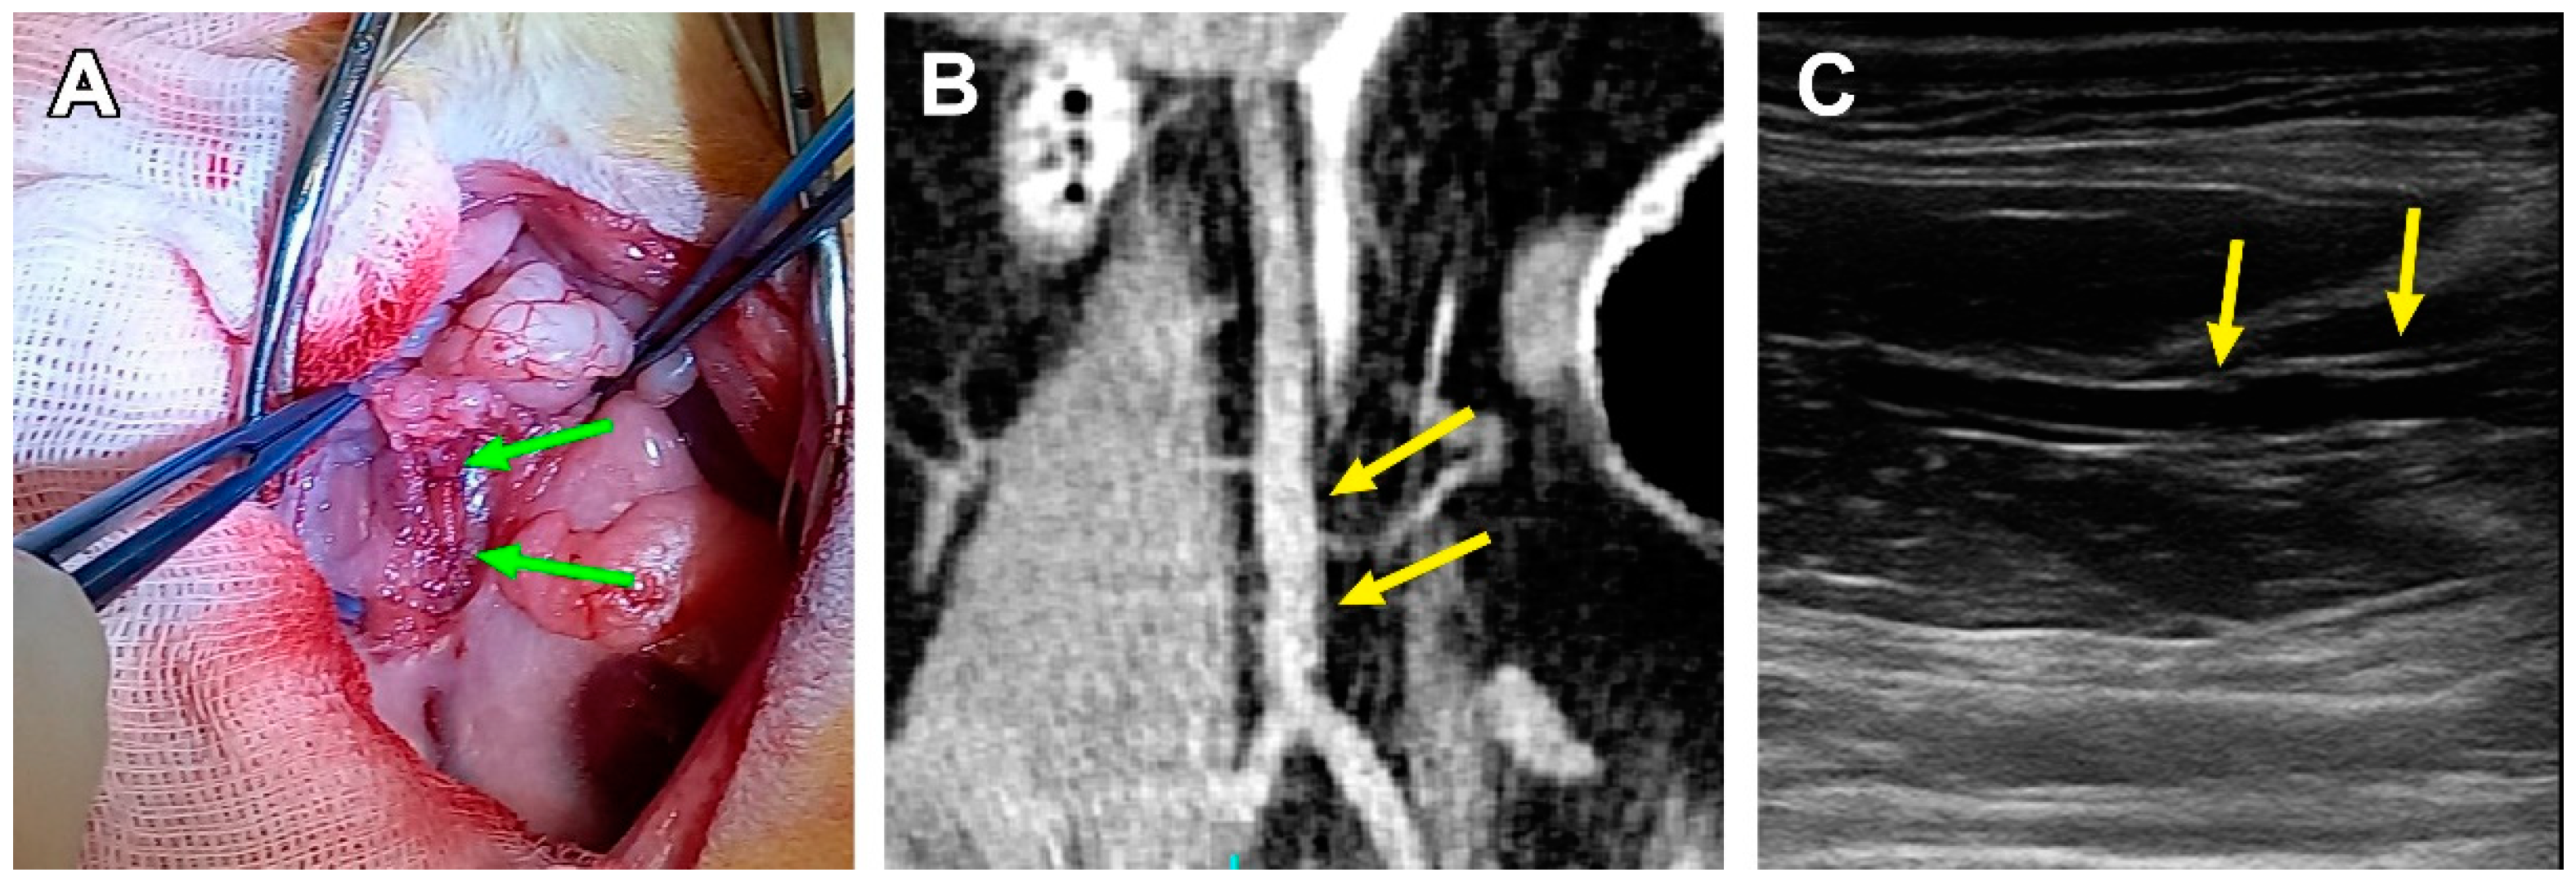

3.2. Surgical Outcomes

3.3. PCL Scaffold Transformation

4. Discussion